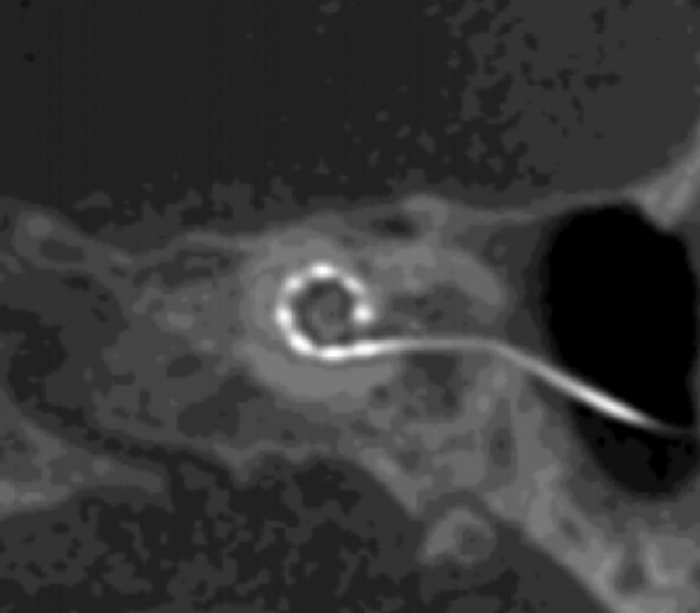

Implantees undergo a computed tomography image postoperatively to determine the position of each electrode in the cochlea more accurately. By mapping the distance from each electrode to the cochlear modiolus, channel interaction can be reduced, deactivating electrodes to improve spatial selectivity (Figure 1). Their latest study showed promising outcomes using all cochlear implant manufacturers [3]. Combined with similar studies looking at manipulating frequency allocation tables to replicate pitch match perception, this new method may change the way we map cochlear implants in the future.

Figure 1. Computed tomography image of a cochlear implant array of electrodes in-situ.